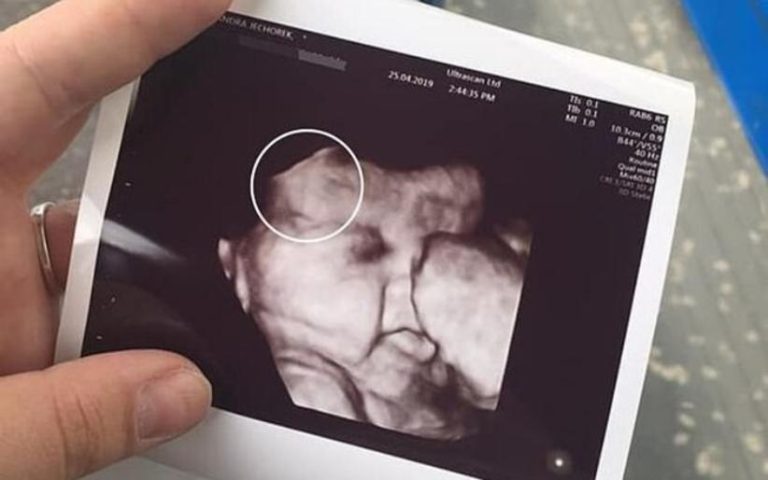

Grávida faz ultrassom e fica chocada com o que vê em bebê